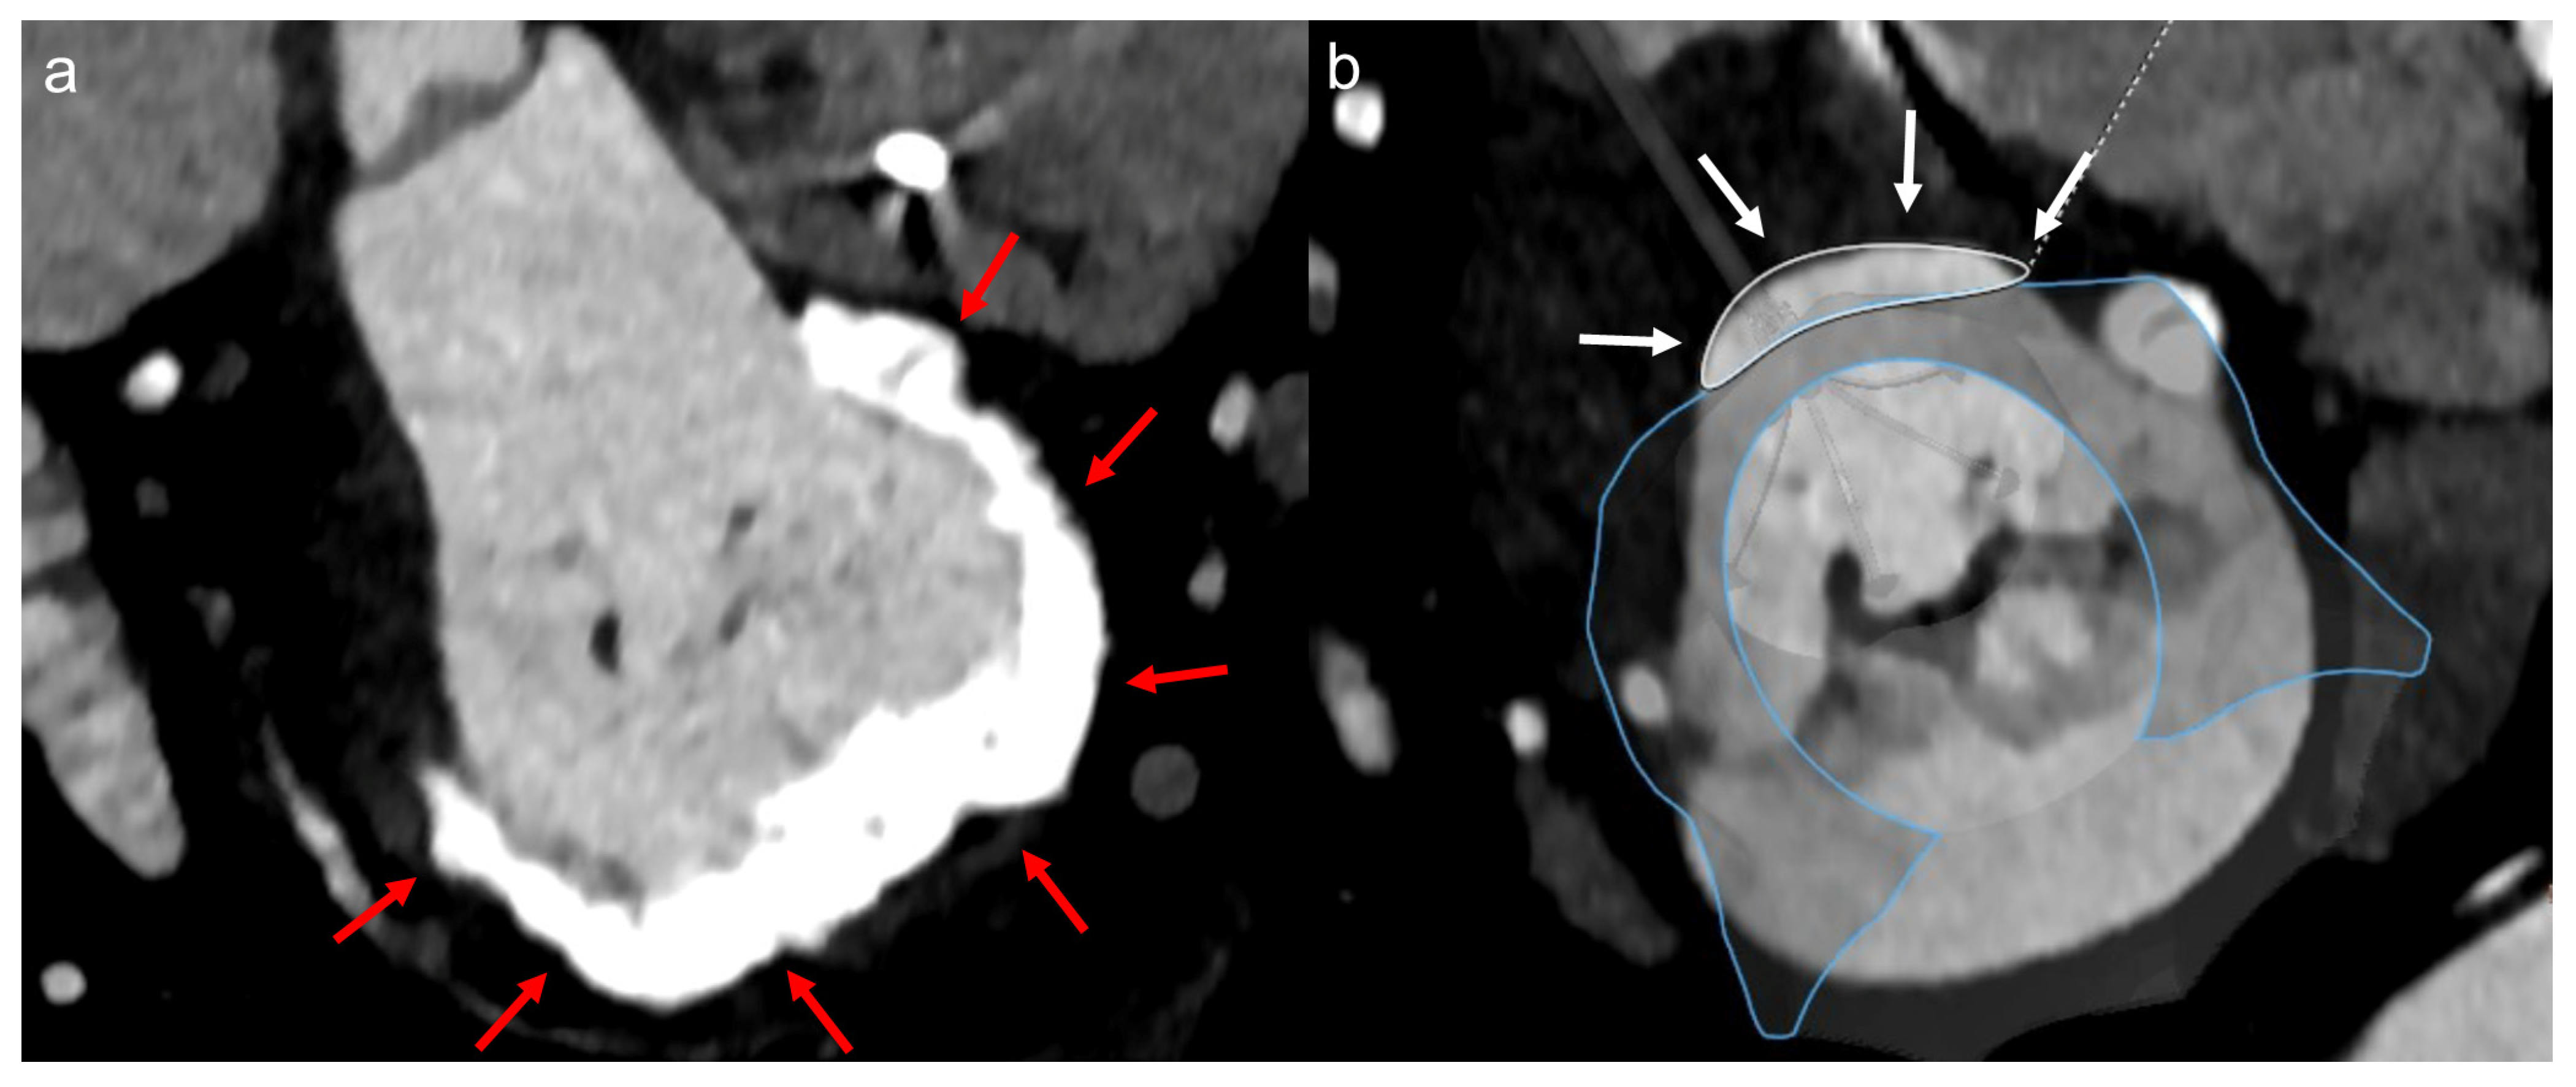

2.2. Echocardiographic Assessment

2.3. Computed Tomographic (CT) Assessment